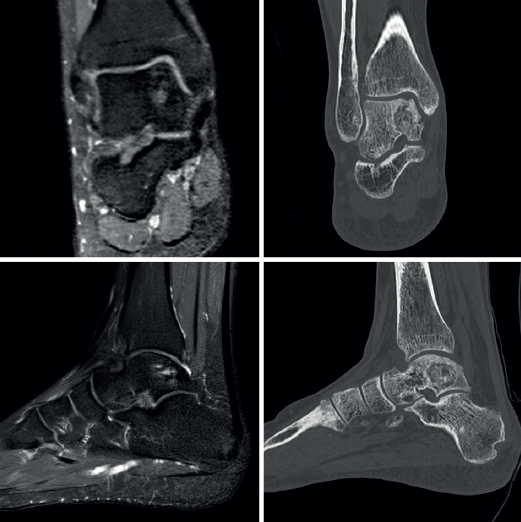

Se realizó un estudio y una planificación preoperatoria pormenorizados del caso, obteniendo una recreación digital de la lesión. Se diseñó una guía a medida con la angulación y el calibre de canal necesario para el instrumental escogido, así como orificios para su fijación con agujas de Kirschner de 2 mm. Se obtuvo a partir de tecnología de fabricación aditiva el biomodelo a escala 1:1, así como el mismo modelo adaptado al tobillo del paciente (Figura 4).

El paciente inicia la movilización activa y pasiva supervisado por un fisioterapeuta a la tercera semana. Realiza descarga por espacio de 6 semanas, seguida de carga parcial progresiva según la tolerancia. Presenta mejoría del control del dolor respecto a la situación preoperatoria (EVA: 8 → 1) y mejoría en la escala funcional (AOFAS: 59 → 90) tras 4 meses de tratamiento. Se realizan controles radiográficos a la cuarta y la décima semana de la intervención. Se realiza estudio por TAC a los 4 meses y al año de la intervención. Se realiza estudio por RM al año de la intervención quirúrgica. Los controles radiológicos muestran preservación de la superficie articular tibioastragalina y relleno de la cavidad quística (Figuras 7 y 8).